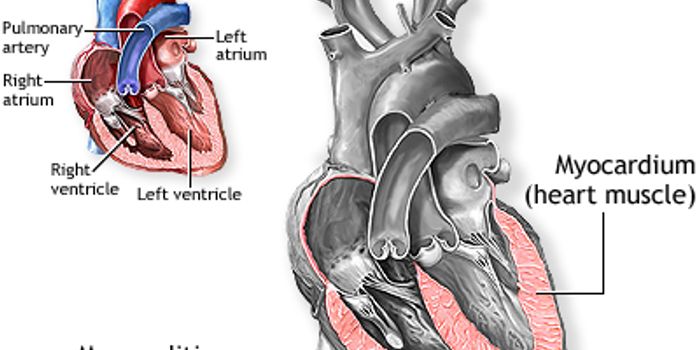

MAR 13, 2016CardiologyThe healthy, beneficial bacteria that live in the human gut break down choline and produce a compound called TMAO while ...